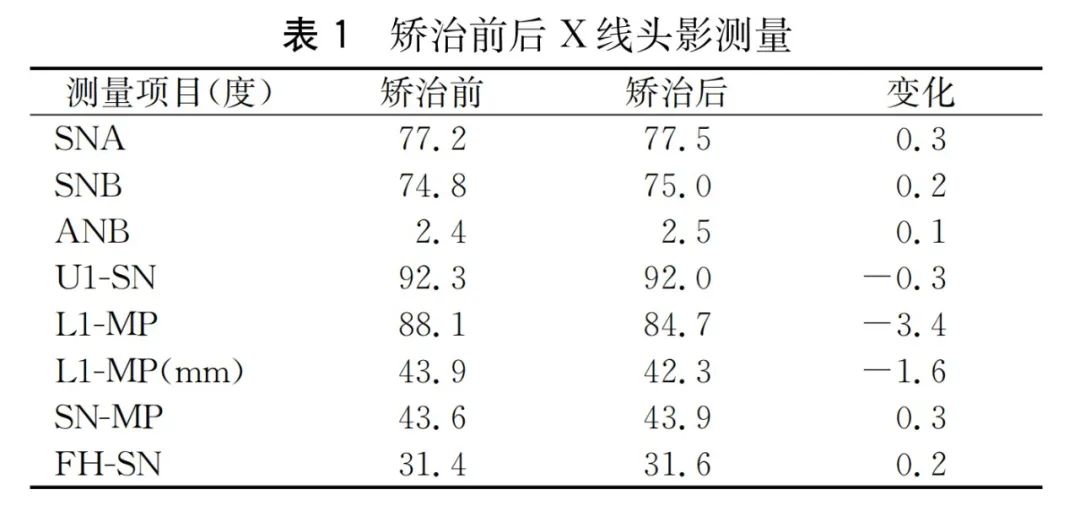

治疗前曲面断层片:右上中切牙残根。右下第一磨牙大面积高密度充填体及髓,未见根充影像,近中根尖低密度影环绕。头影测量见表1。

联合治疗结束后患者面型没有改变,双侧尖牙及磨牙为中性关系。下牙列排齐并压低,前牙覆(牙合)覆盖正常。双侧颞下颌关节未发现弹响及压痛。曲面断层片未见明显的下前牙牙根吸收。头影测量显示下前牙舌向移动并压低,下颌平面角没有明显的改变(图5)。